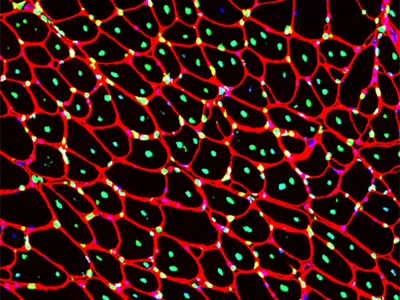

Myoblasts and macrophages are required for therapeutic morpholino antisense oligonucleotide delivery to dystrophic muscle

Novak JS, Hogarth MW, Boehler JF, Nearing M, Vila MC, Heredia R, Fiorillo AA, Zhang A, Hathout Y, Hoffman EP, Jaiswal JK, Nagaraju K, Cirak S, Partridge TA PMID: 29038471 Nature Communications 8:941 (2017)